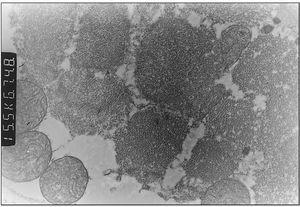

Exploraciones complementarias: hemograma normal; velocidad de sedimentación globular (VSG), 14 mm; bioquímica con normalidad de glucosa, calcio e iones; bilirrubina total, 5,2 mg/dl; bilirrubina directa, 1,1 mg/dl; GOT, 100 U/l; fosfatasa alcalina, 993 U/l, lactato deshidrogenasa (LDH), 708 U/l. Equilibrio acidobásico: pH, 7,33; presión parcial de dióxido de carbono (pCO2), 57; y de oxígeno (pO2), 50; bicarbonato, 30; exceso de bases, 4. Citoquímica y cultivo de líquido cefalorraquídeo (LCR): negativos. Enolasa neuroespecífica en LCR: 32 μg/ml (aumentada). Proteína básica de mielina en LCR: 0,3 ng/ml (0-1,5 ng/ml). Perfil de aminoácidos en sangre y orina: normales. Ácido láctico, 26,1 mg/dl (3-15 mg/dl), y ácido pirúvico, 1,6 mg/dl (0,3-1 mg/dl), aumentados en sangre. Cociente lactato/piruvato, 16. Ácido acetoacetato y 3-hidroxibutirato, aumentados. Ecografía cerebral, normal. Fondo de ojo, normal. Electroencefalograma: actividad de fondo lentificada con puntas aisladas parietotemporales izquierdas. Resonancia magnética (RM) cerebral: alteraciones de intensidad de señal (aumento en T2) bilateral y simétrica en núcleos lenticulares, tálamos, núcleos rojos mesencefálicos y protuberancia así como vermis inferior, con ausencia de mielinización en sustancia blanca de circunvoluciones pre y poscentral (fig. 1). Biopsia del músculo estriado: fibras tipo 1 con disminución anular subsarcolémica de la actividad oxidativa. Al microscopio electrónico: ausencia de fibras rojas rasgadas y presencia de fibras musculares con mitocondrias de tamaño aumentado compatible con probable anomalía mitocondrial (fig. 2). Estudio de función mitocondrial en homogenado muscular: déficit de los complejos I, III y IV de la cadena respiratoria (tabla 2).

Figura 2. Biopsia muscular: aspecto con microscopia electrónica. Megamitocondrias (0,9μ) de tamaño algo inferior a las miofibrillas (x31.000).